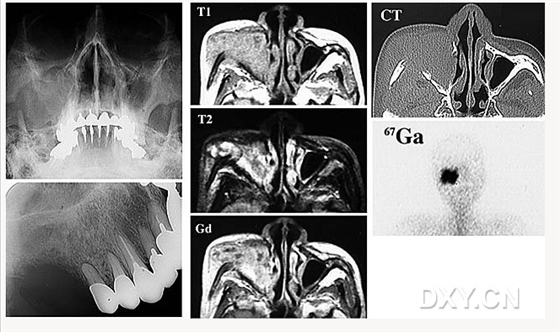

骨肉瘤

涎石病